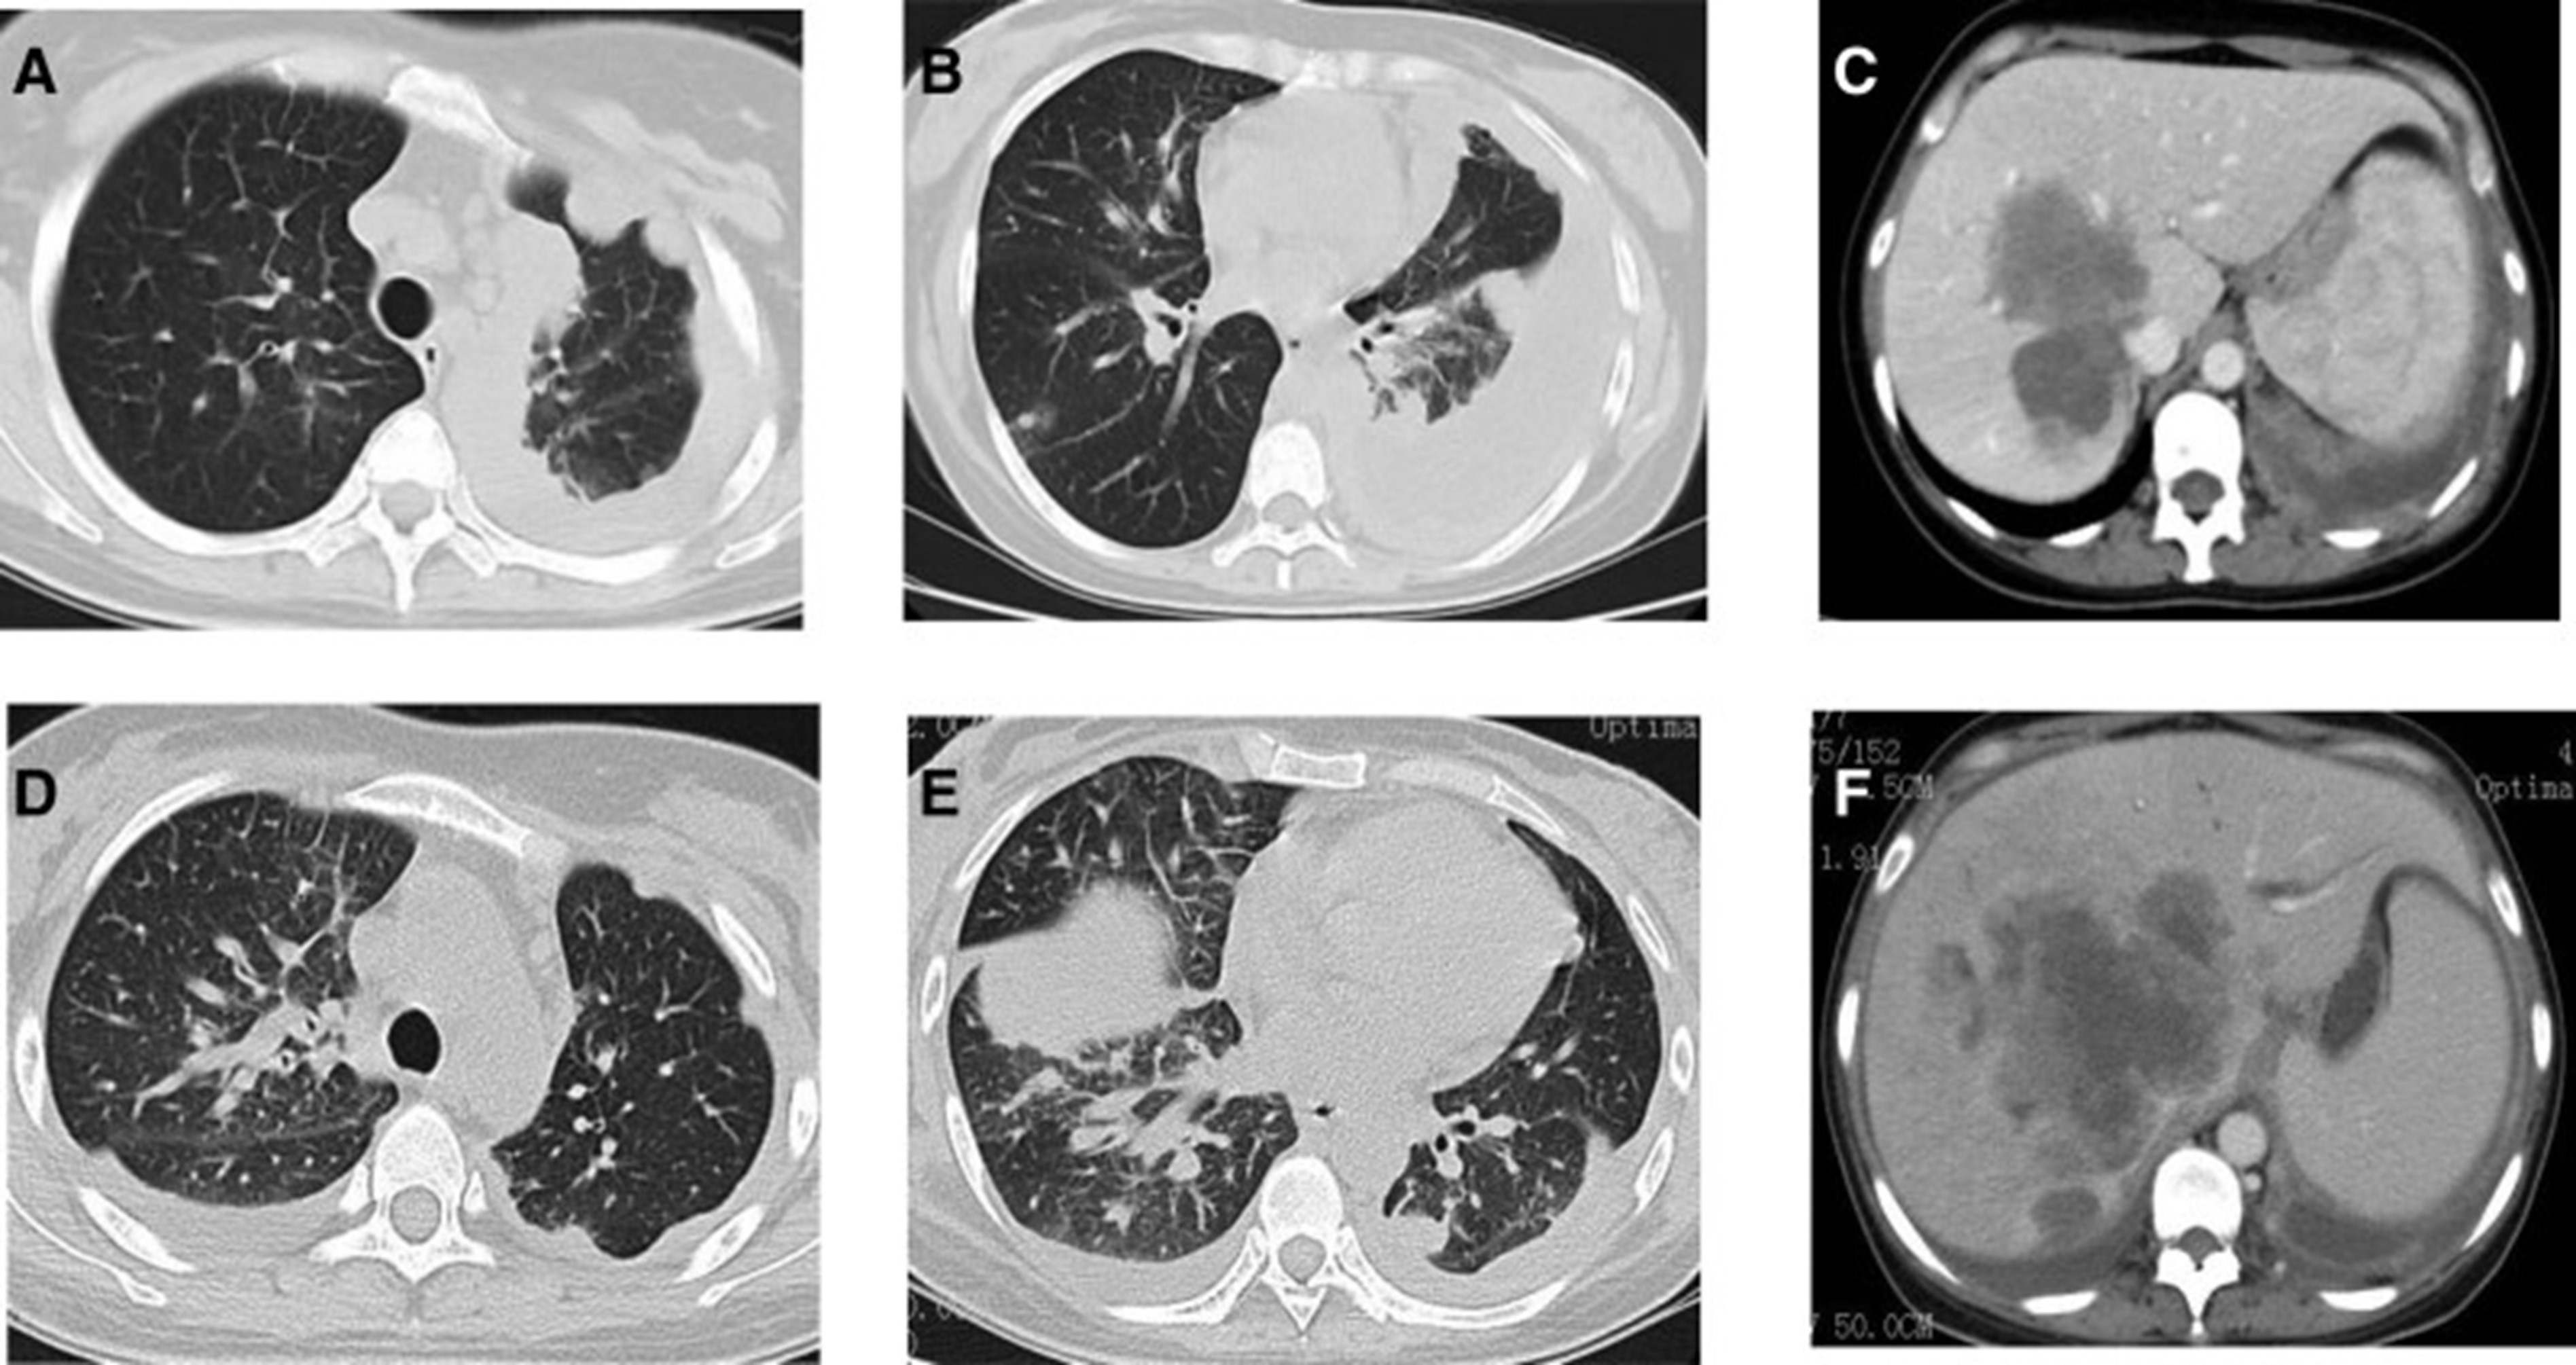

2020年4月,患者胸部CT示“双肺多发结节,纵隔及肺门多发肿大淋巴结;附着于肝右叶,略呈低密度肿块影”(图 1)。(图4A,4A、B)和腹部CT显示“肝脏多发肿块”(图1)。(图 4C)。骨扫描显示“身体多个部位的骨代谢异常增强”。2020年4月19日,对“右肝肿块和右锁骨上肿块”进行活检,病理指征(右肝肿块抽吸、右锁骨上肿块抽吸)为低分化腺癌。结合免疫组化结果,首先考虑的是肺腺癌转移。贼终诊断为“IV期肺腺癌伴多发肝和骨转移”。基因检测显示“EML 4-ALK 融合,PD-L1 肿瘤阳性细胞数TPS 80%”(图 2)。(图1和和2)。

和 2020 年 6 月 (D-F).jpg)

图 4:2020 年 4 月 (A-C) 和 2020 年 6 月 (D-F) 的 CT 扫描。CT = 计算机断层扫描。

2020年5月1日,患者开始口服艾乐替尼靶向药物进行治疗,2020年6月25日复查,确定治疗效果为PR(部分有效)(根据RECIST1.1)显示肺病灶和肝转移灶明显减少(图1)。(图 3D-F)。2020 年 8 月 27 日复查确定治疗效果为疾病进展(PD, progressive disease),根据 RECIST1.1显示肝脏病变变大(图 1)(图 4A-D)。进行了第二次肝活检,随后的病理学显示“(肝)低分化癌,结合免疫组织化学分析考虑肺腺癌转移”。组织活检进行了第二轮基因检测,结果显示“BRAFV600E 14.79%,EML 4-ALK fusion 14.47%”(图 1)(图 5)。2020年9月20日,对患者我以为用恩沙替尼联合达拉非尼靶向治疗。治疗开始后,患者出现明显发热、寒战、乏力和厌食。期间患者左侧出现大量胸腔积液,胸腔积液中脱落细胞为“非典型细胞,考虑为腺癌”。随后,该患者接受了 1 次胸腔内铂输注。

和 2020 年 8 月.jpg)

图 5:2020 年 6 月(A 和 B)和 2020 年 8 月(C 和 D)的 CT 扫描。CT = 计算机断层扫描。

1个月后复查显示肺部和肝内病变进展(图1)。(图 6A-C)(根据RECIST1.1),她的抗肿瘤治疗改为“培姆曲塞加卡铂和贝伐单抗”的治疗一个周期。2020年12月至2021年1月,再次改变患者的治疗方案,这次改为“劳拉替尼联合达拉非尼”靶向治疗。使用 PD 联合胸部和腹部 CT 评估疗效(图 1)。(图 6D-F)(根据 RECIST1.1)。患者无法耐受化疗、靶向治疗、IO 治疗或任何其他积极的抗肿瘤治疗。这是因为患者的一般情况较差,包括发烧、腹痛和胆红素水平升高等症状。随后,给予患者静脉营养、镇痛等对症支持治疗。患者于 2021 年 2 月 4 日去世,总生存期(OS)为 10 个月。

和 2022 年 1 月 (D-F) 的 CT 扫描.jpg)

图 6:2020 年 11 月 (A-C) 和 2022 年 1 月 (D-F) 的 CT 扫描。CT = 计算机断层扫描。